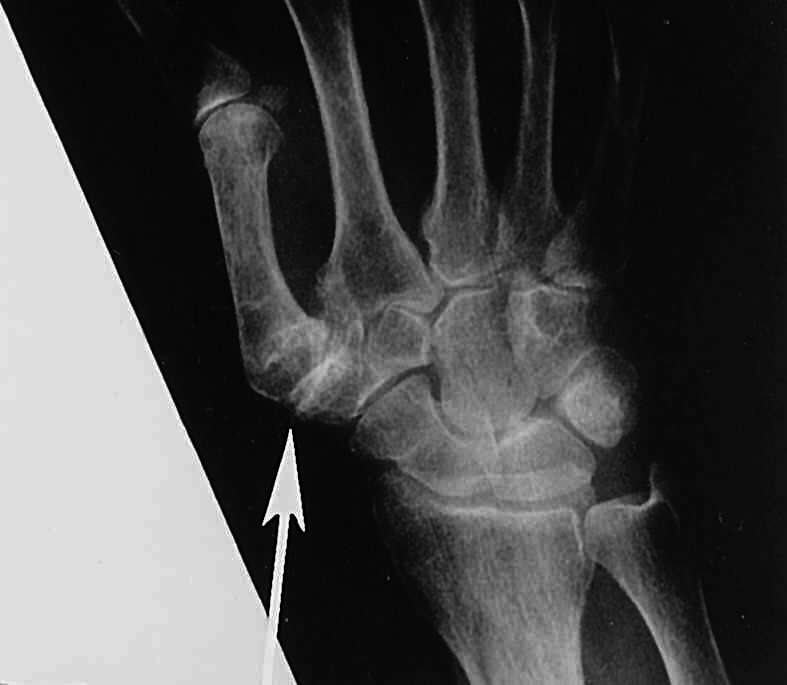

From www.e-hand.com

From www.eatonhand.com

From www.researchgate.net

From www.semanticscholar.org

Arthritis Basal joint arthritis Degenerative Basal Joint thumb arthritis is a common condition that affects the carpometacarpal (cmc) joint at the base of your thumb. thumb arthritis is a common type of osteoarthritis that affects the basal joint at the base of your thumb. learn about the symptoms, causes and diagnosis of thumb arthritis, a common condition that affects the joint at the base. Degenerative Basal Joint.